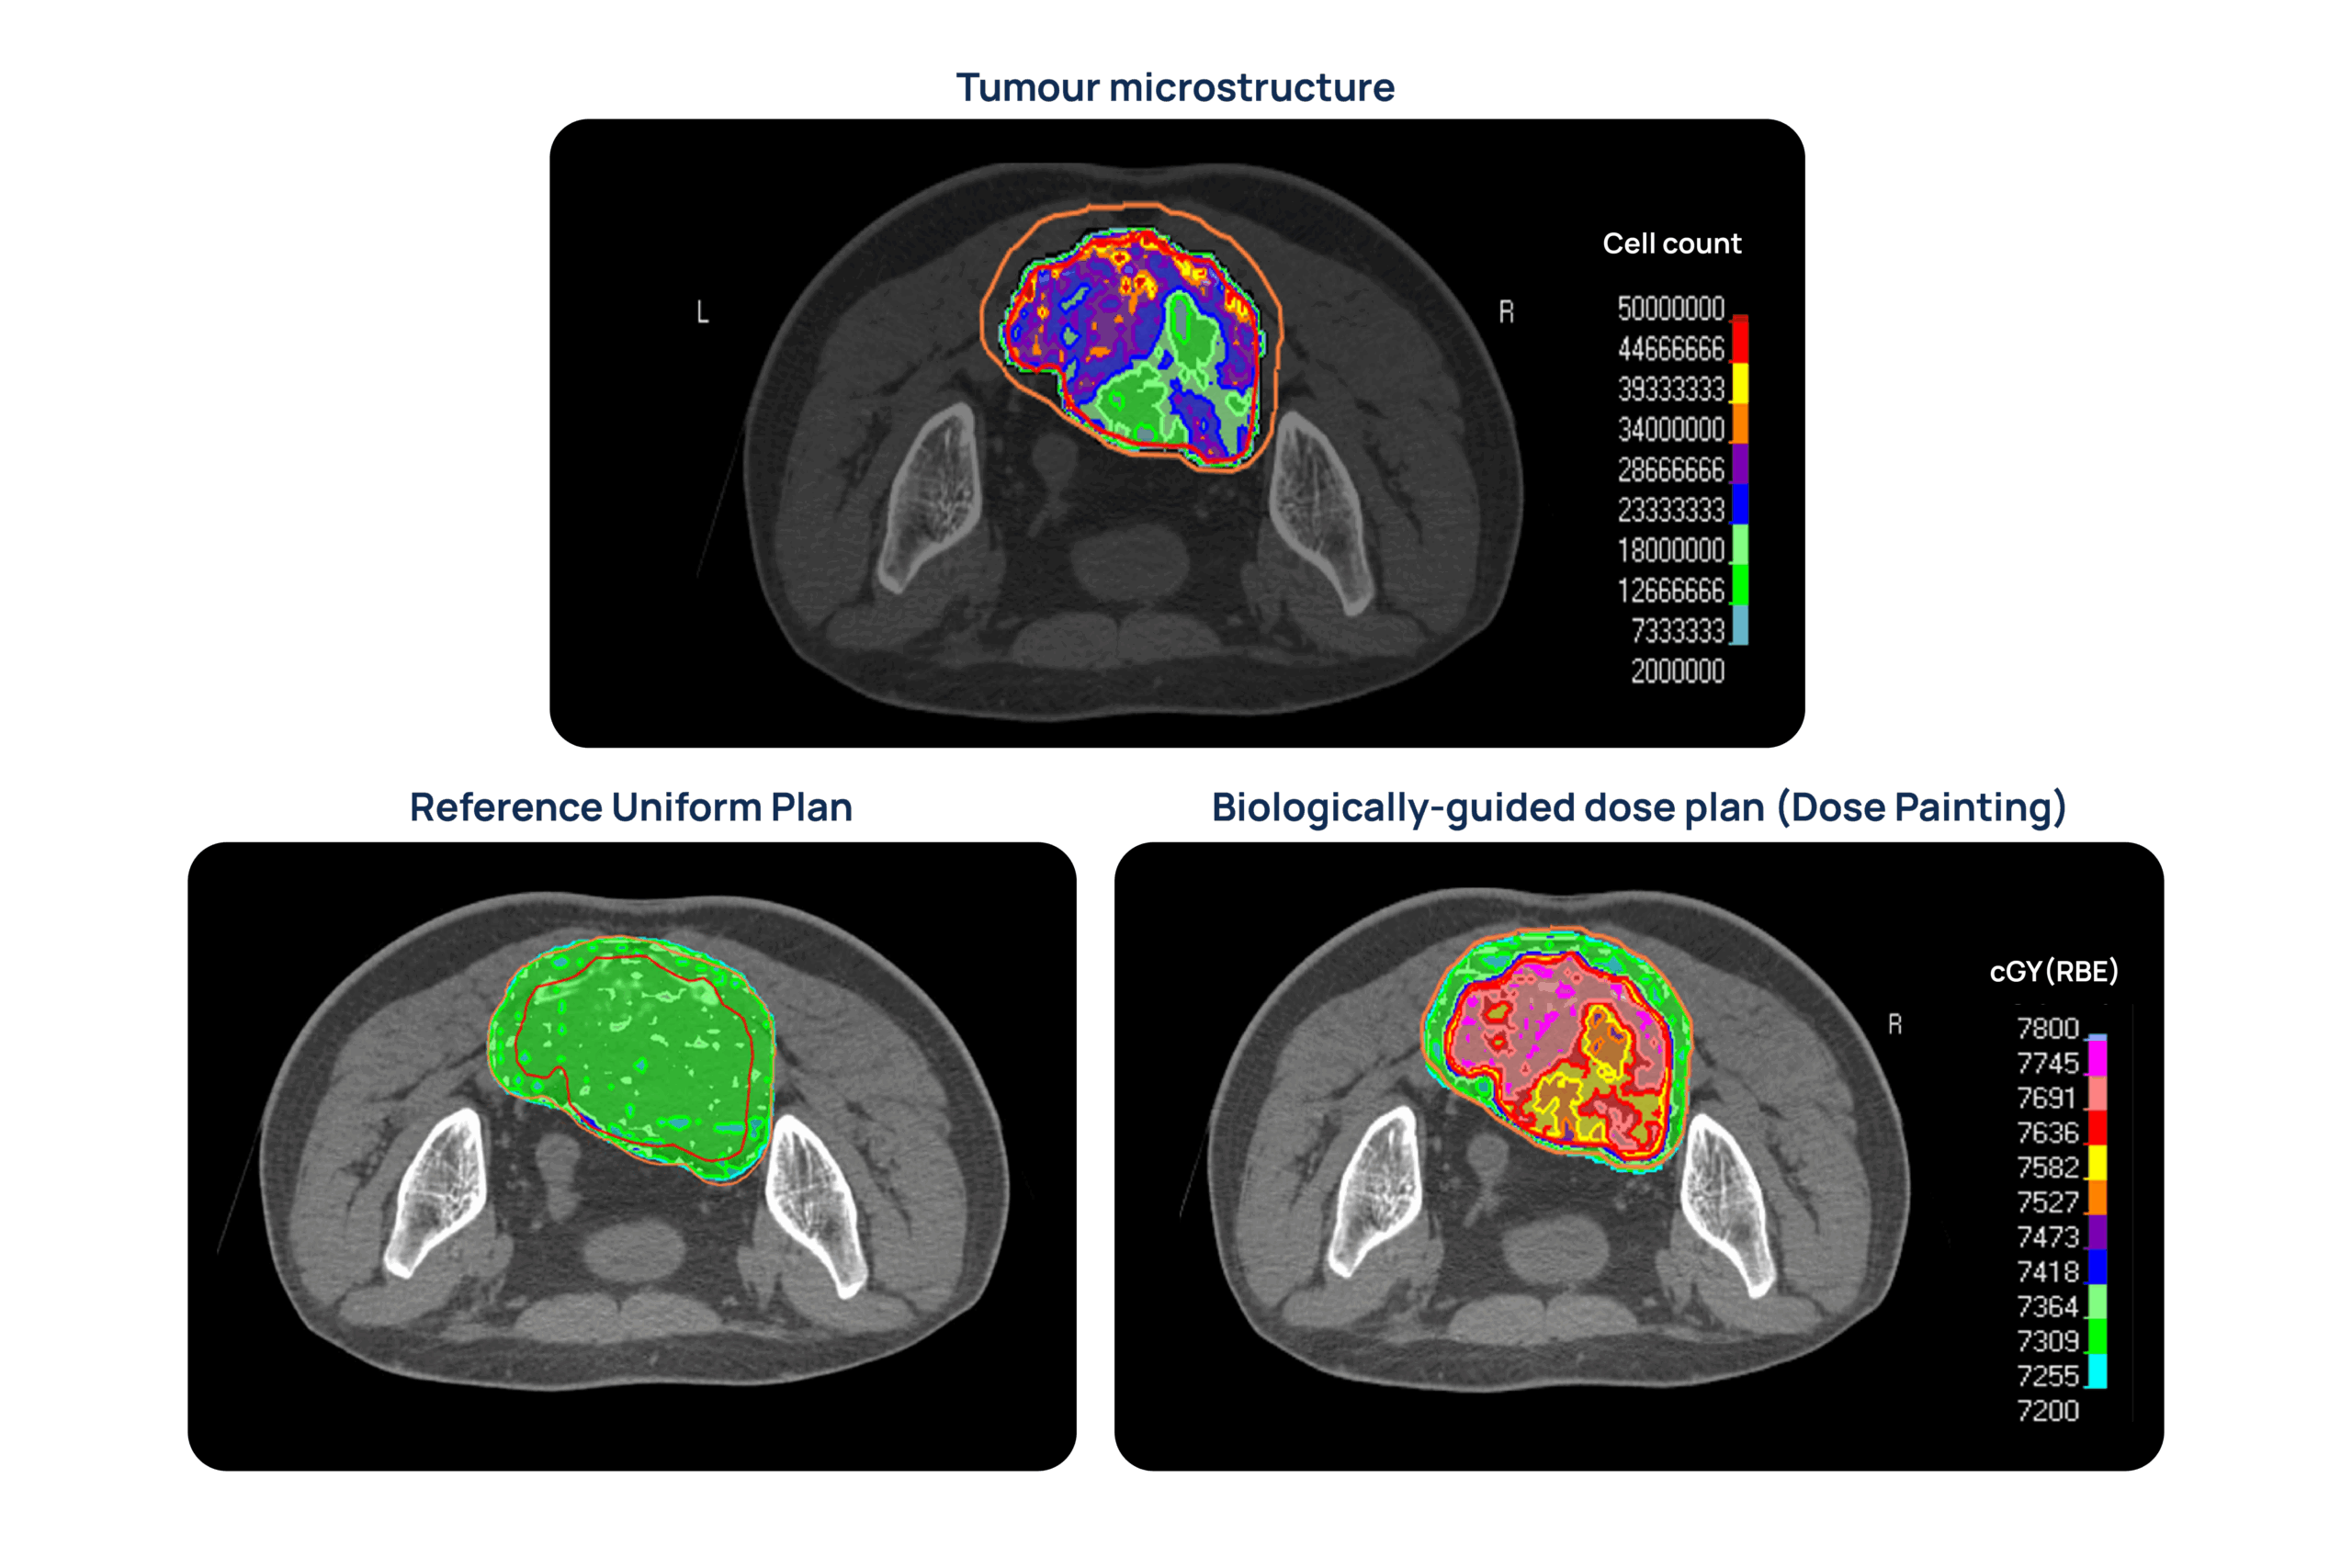

The AI and MC-based models trained in previous work packages will be applied to clinical datasets to derive personalized maps of tumor microstructure and radiobiology. Results will be compared with clinical information for correlation and predictive value. Moreover, the derived microstructural and radiobiological information will be used to implement personalized tumor control probability models towards biologically-guided dosimetric treatment plans.